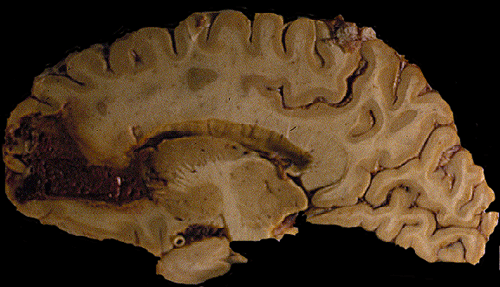

Gross: On external examination of the body, there was no bruising, hemorrhage, or other signs of trauma. The brain weighed 1,300 grams. The cerebellum and brainstem were within normal limits. A large hemorrhage was present in the right frontal lobe (Panel A). The hemorrhage is rimmed by a thin layer of golden brown tissue indicative of hemosiderin deposition that would be produced by old, resolved hemorrhage  (White arrow in Panel A). The hemorrhage also extends into the ventricle, without dilating the ventricles, and into the basal subarachnoid space (Black arrow in Panel A). On the left frontal tip and bilateral temporal tips, there were some small areas of golden brown discolorations in the leptomeninges that were consistent with resolved small subarachnoid hemorrhages.

Comment on gross pathology: The golden brown discoloration in the leptomeninges of the temporal tips is probably due to small hemorrhage because of minor falls as the patient has been alcoholic. The question is whether the large hemorrhage related to his fall. The hemorrhage can be produced by trauma but the extent of hemorrhage, however, seems to be out of proportion to a minor trauma as described by the family members of the deceased patients. Since the fall has occurred 2-3 weeks before, the hemosiderin deposition may be resulted from the hemorrhage triggered by that fall. It can also be resulted from prior hemorrhages. The center of the hemorrhage had some spongiotic changes that could suggest a ruptured hemangioma. Other etiologies including coagulopathies, cocaine abuse, vascular malformations and hemangiomas, and vasculopathies were also entertained. The lack of hemorrhagic lesions in other parts of the brain and the body does not support a diagnosis of coagulopathy.

Grossly, the smaller hemorrhage tends to be superficial rather then deep. For large hemorrhages that have deep extension, it may not be possible to tell whether the epicenter of hemorrhage is superficial or deep. Their superficial location tends to make a small amount of subarachnoid hemorrhage. Extension into the ventricle is uncommon. Typically, small hemorrhage at different stages of resolution is present. The hemorrhages are found as lobar hemorrhage in the white matter in contrast to the hemorrhages that are found in hypertension and are often found in the basal ganglia. CAA hemorrhage is almost always cerebral with the brainstem and cerebellum rarely affected. This is an interesting phenomenon as the cerebellar folia have a large surface area and numerous leptomeningeal blood vessels. CAA hemorrhagedoes not appear to have a predilection to occur in leptomeningeal vessels although these vessels typically contains amyloid deposition in the wall.